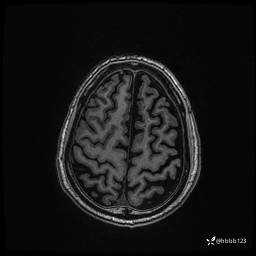

患者男,43岁。

简要病史:癫痫患者复诊,昨日发作5-6次,建议住院进一步治疗。

入院完善脑癫痫组合序列:

3d T1: